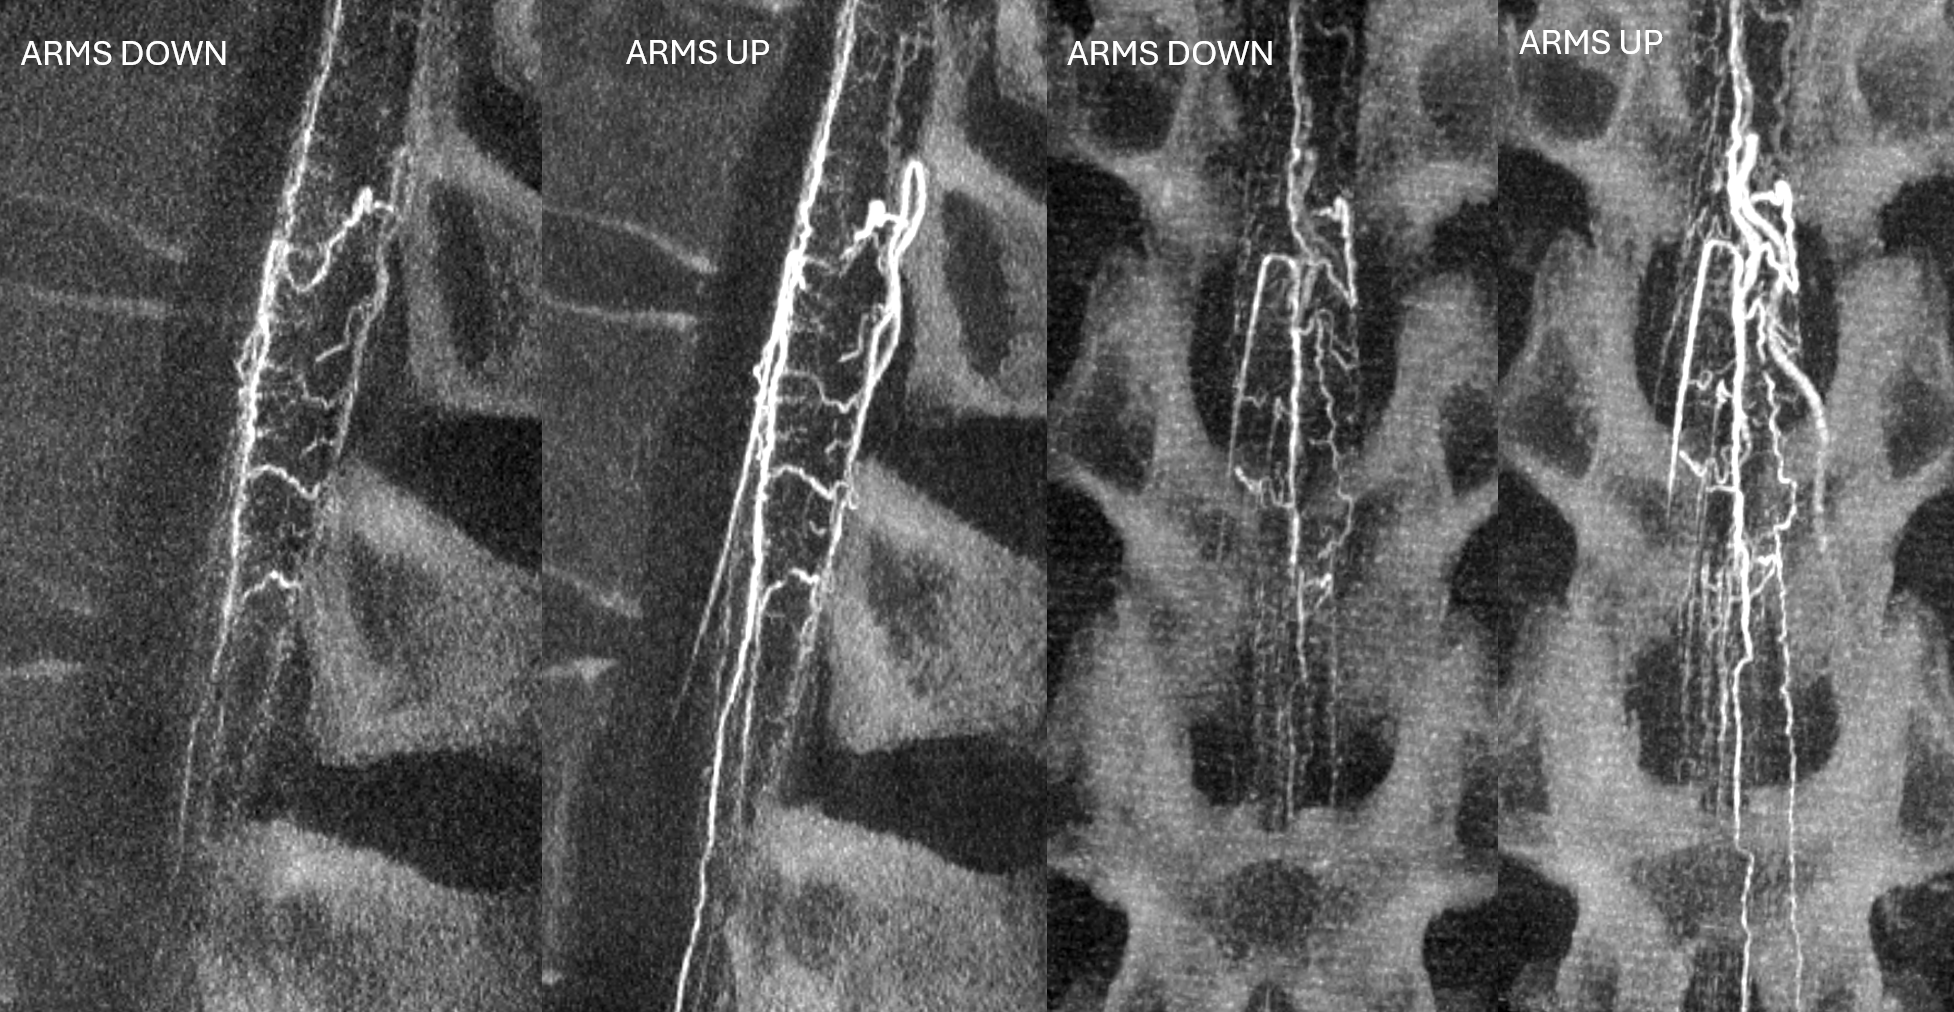

MIPS

The difference is even more striking in venous phase. Selecting venous delay is key. The delay is chosen based on the time between the END of arterial opacification and beginning of venous one

Arms DOWN, arterial phase. Siemens Icono, 7 second micro dyna single volume, 1 cc/sec for 8 seconds, 13 second delay.

Arms UP, arterial phase. Siemens Icono, 7 second micro dyna single volume, 1 cc/sec for 8 seconds, 13 second delay. It could have been even better if wires and EKG leads were moved.

Venous MIPs